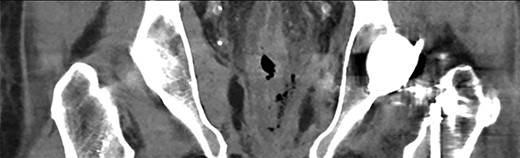

In retrospect, the patient reported anal pain during administration of a fleet enema 3 days prior. On inspection of the anus, there was a necrotic area leading into the anal canal. This finding of perianal trauma associated with the increasing evidence of sepsis led to a presumptive diagnosis of FG. CT scan (Fig. 2) demonstrated an area of hazing and small amounts of free gas within the perirectal tissue suggestive of a rectal perforation or FG. The patient was taken to theatre for an urgent intervention. The scrotum and perianal region required debridement of the affected soft tissue (Fig. 1). Sigmoidoscopy demonstrated circumferential necrosis of the lower portion of the rectum consistent with REI (Fig. 3). A decision was made to expectantly manage the rectal injury and perform a repeat sigmoidoscopy with the aim of preserving the rectum in lieu of an urgent rectal resection. The antibiotic regime was changed to meropenem, clindamycin and vancomycin. Tissue cultures from the debridement grew scant colonies of Pseudomonas aeruginosa and Bacteroides uniformis. The repeat sigmoidoscopy demonstrated stabilization of the rectal ischaemia. A diverting colostomy was created to assist in application and management of negative pressure dressings to the perineal wound (Fig. 4). He required 2 days of post-operative ICU support and over the next 2 weeks, symptoms and inflammatory markers returned to normal. An examination under anaesthesia performed 1 week later demonstrated interval improvement of the rectal mucosa with resolving necrosis. The patient was discharged after 3 weeks with no further dressings and the colostomy was reversed 3 months later.

Coronal CT image demonstrating contained, localised rectal perforation secondary to enema injury.